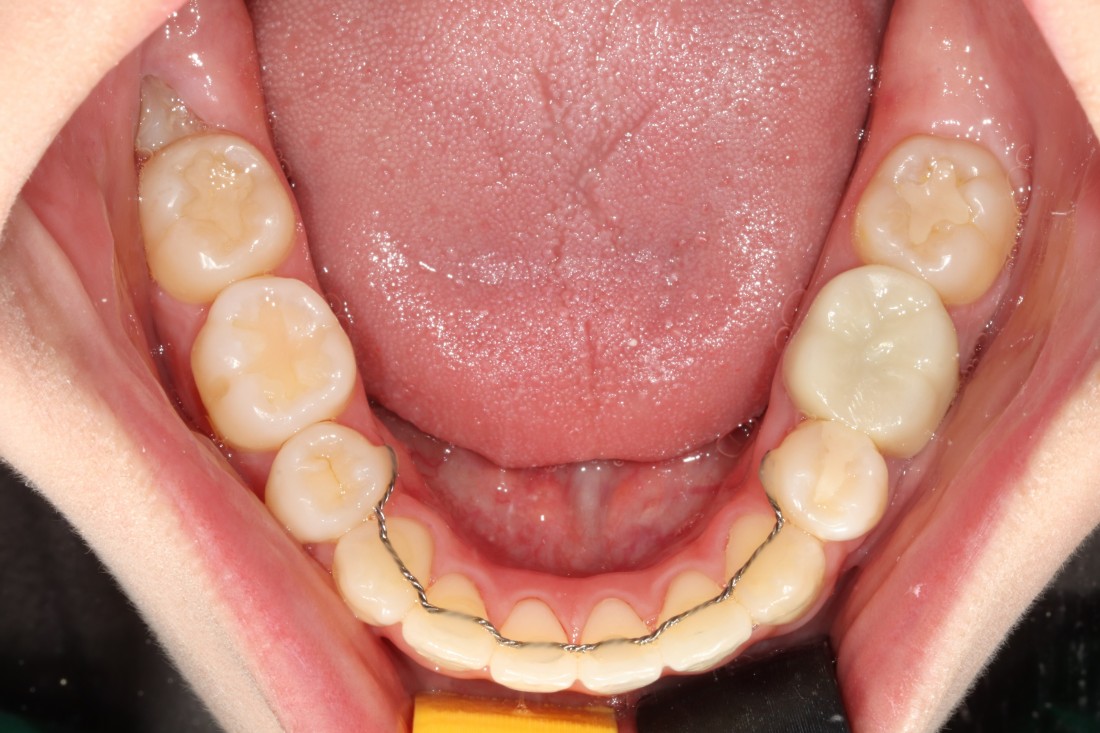

광주 성인 교정치과에서

충치치료와 교정진료를 동시에 받으신

성인 여성 환자분의 케이스입니다.

충치치료 전에는 은색 보철물이 있던 자리에

교정진료의 마무리와 동시에

치아색 보철물을 씌워서

치아교정 + 충치치료를 동시에 진행하였습니다.

광주 성인 치아교정의 경우

충치치료의 시기를 잘 판단하여

성공적인 진료를 완성할 수 있기 때문에

분과별 전문의가 협진하는

광주 성인 교정치과를 선택하시는 것이 좋습니다.